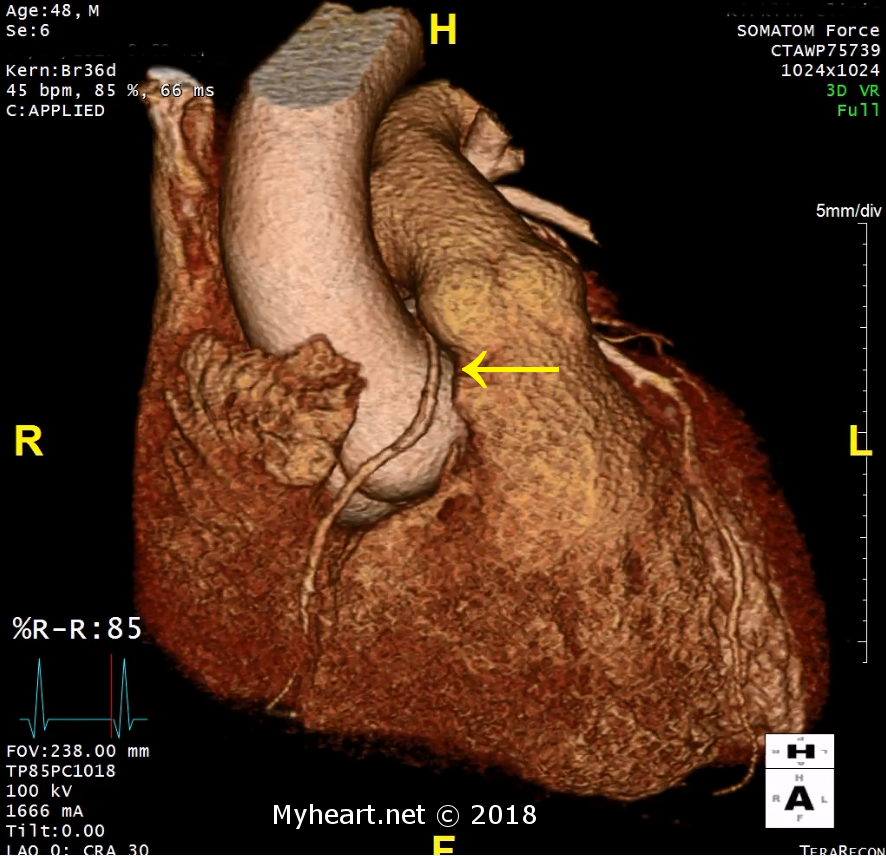

We are on a mission to change how our students learn about anatomic pathology by using real CT and MRI images to create models to better teach our students.

On the right: Printed models of hypoplastic left heart syndrome and pulmonary atresia.

We are creating a 3D printed library of anatomic models of pathology for our medical students.

At the CIAV we have to see it to believe it. We believe that visualization and tactile manipulation of pathological anatomic specimens is key to sustained knowledge acquisition.